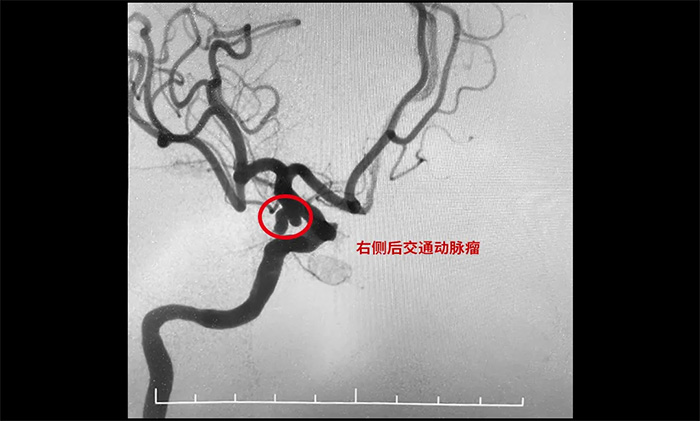

《长江日报》2023年10月18日报道,55岁的张女士参加家庭聚会唱《青藏高原》飙高音时,突然头疼剧烈、恶心呕吐,家人紧急将其送医。医院给她做了全脑血管造影,最后发现是动脉瘤破裂。

▲ 栓塞前